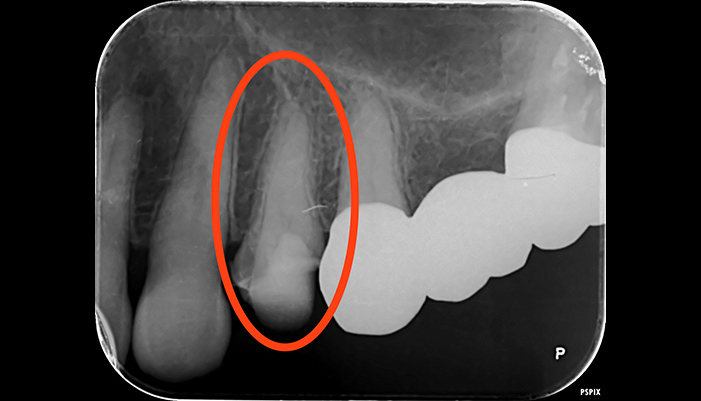

治療前

治療後

| 主訴 | 虫歯がある。根の管が細すぎて見当たらない。 |

|---|---|

| 治療期間 | 1回 |

| 費用 | 再根管治療132,000円(税込)+ ファイバーコア44,000円(税込)= 176,000円(税込) |

| 治療内容 |

ラバーダムを用いて無菌的な環境下で根管治療を行いました。 マイクロスコープ下で虫歯を完全に取り切り、根の管の細さが0.06mm程度になっていたため慎重にNiTiファイルを用いて根管形成を行い、 薬液や超音波器具による洗浄、体に馴染みの良い材質による充填、被せ物を支え、再感染しないように土台を立てました。 |